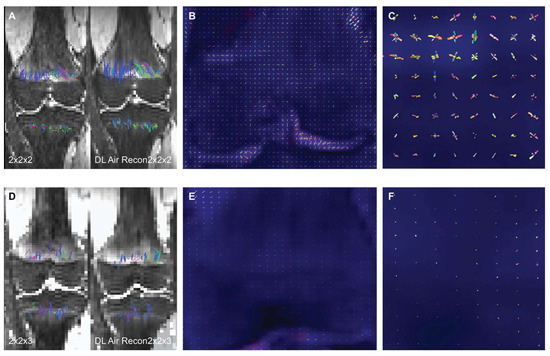

2.3. Intra-Voxel Tensor Visualization at Different Spatial Resolutions